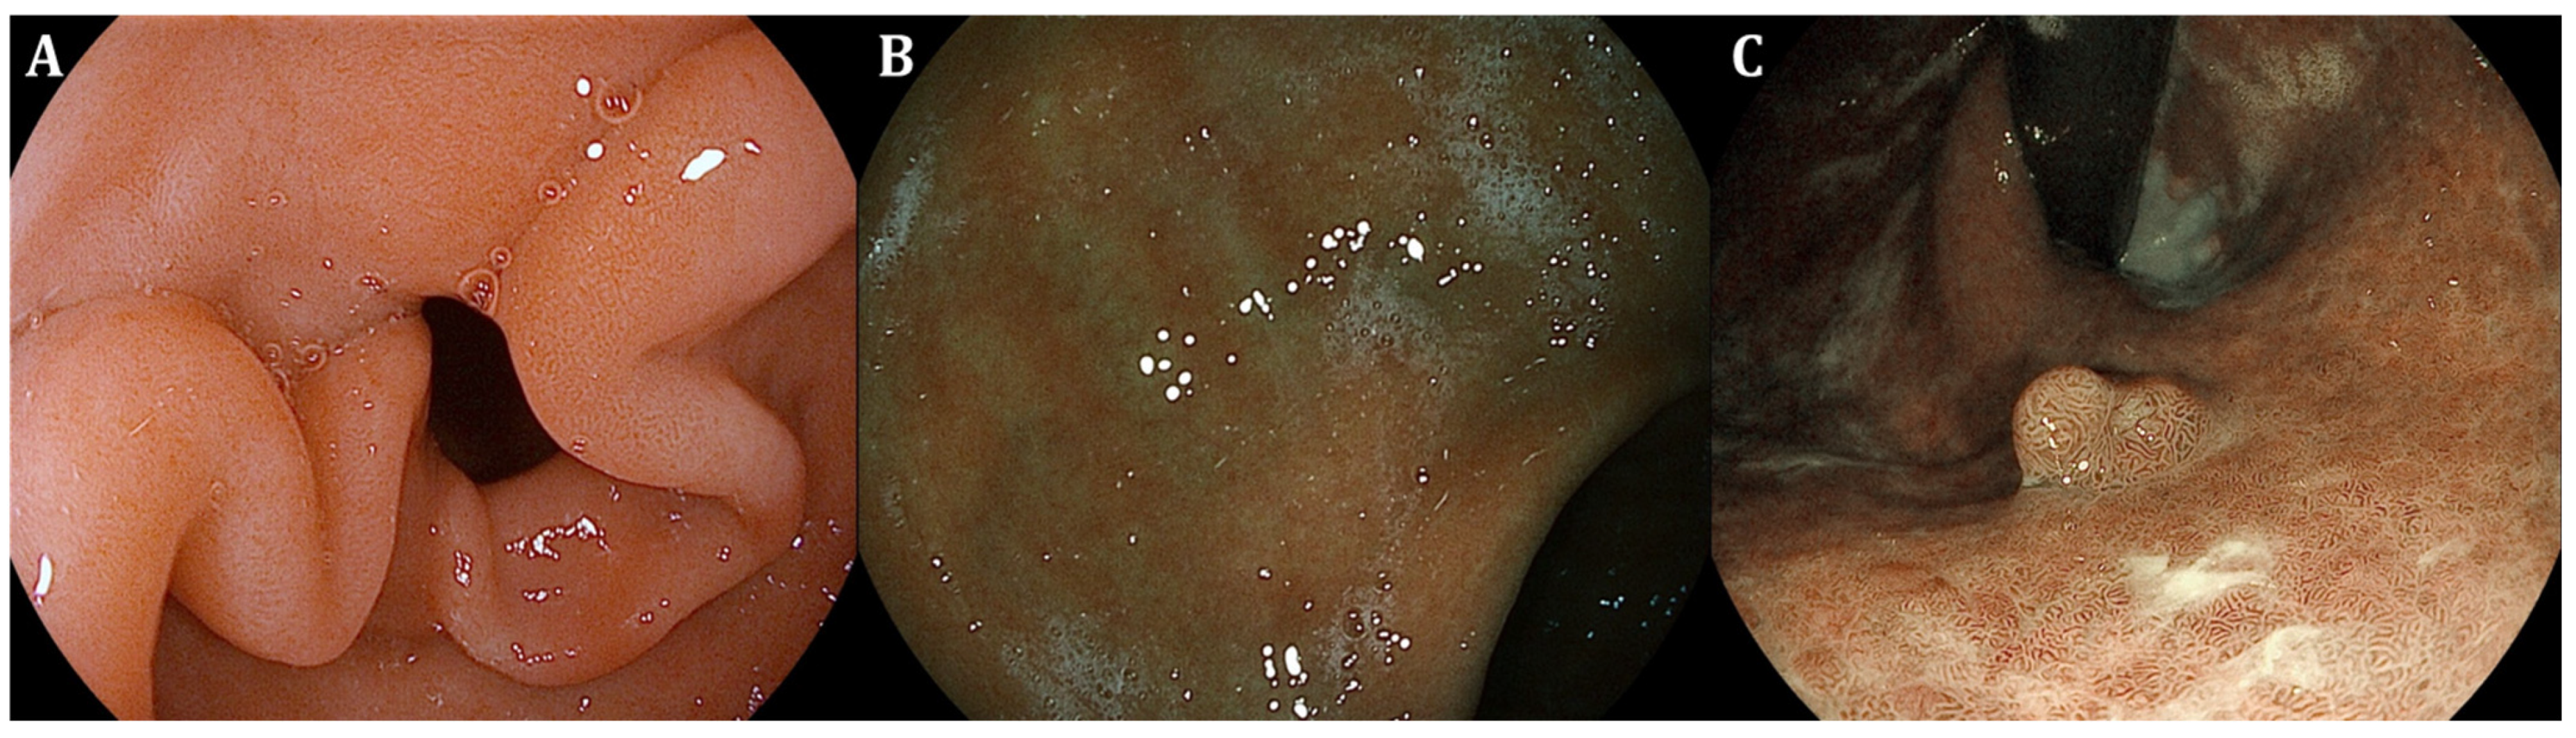

| GIM endoscopic findings | Light-blue crest (LBC) as fine blue–white line on the crest of the epithelial surface, white opaque substance (lipid droplets) obscuring the subepithelial capillaries, multiple pale, elevated patches | Elevated greyish white patches surrounded by pale and normal-color gastric mucosa or blotchy patchy erythema, lipid droplets termed white opaque substance (WOS), patchy reflections of blue–white located on epithelial margins termed light-blue crest | Lavender area, “Lavender color sign” (LCS); “Purple in Mist” (purple mixed with white on the epithelium, with signs of mist detected by non-magnifying LCI observation—PIM); “patchy lavender color” (patchy lavender color with a regular mucosal pattern and a clear border—PLC) |